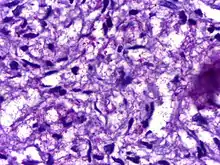

| Microphotograph of Mycobacterium leprae, the small brick-red rods in clusters, taken from a skin lesion. Source: CDC | |

Optical microscopy shows M. leprae in clumps, rounded masses, or in groups of bacilli side by side, and ranging from 1–8 μm in length and 0.2–0.5 μm in diameter.[6] [7][8] The organism has been successfully grown on an artificial cell culture medium on a very limited basis by researcher Arvind Dhople.[4] This can be used as a diagnostic test for the presence of bacilli in body lesions of suspected leprosy patients. The difficulty in culturing the organism appears to be because it is an obligate intracellular parasite that lacks many necessary genes for independent survival. The complex and unique cell wall that makes members of the genus Mycobacterium difficult to destroy is apparently also the reason for the extremely slow replication rate. Virulence factors include a waxy exterior coating, formed by the production of mycolic acids unique to Mycobacterium.